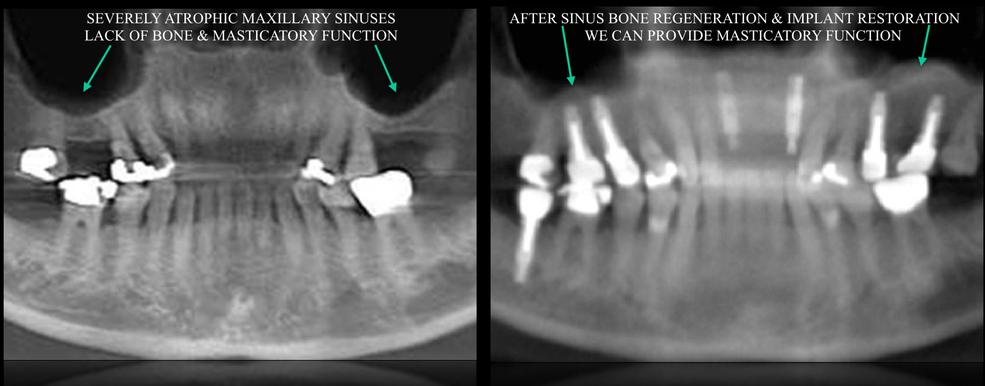

- JAW RECONSTRUCTION ---> RIDGE AUGMENTATION

- MINIMALLY INVASIVE SINUS AUGMENTATION

- DENTAL IMPLANTS TO REPLACE MISSING TEETH